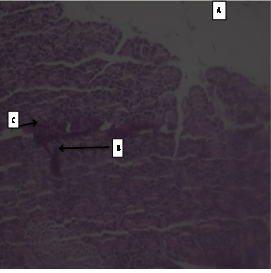

Result of Histopathological studies (fig 4)

The photomicrographs of normal control group rats showed normal acini, and normal cellular population in the islets of Langerhans in pancreas as shown in (slide 1). Massive cell damage, extensive destruction of cell lining, inflammatory cells, and β-cell damage were seen in diabetic control group (slide 2). There was enlargement of β-cells, increase in vascular spaces with hyperplasia in standard group, i. e. Glibenclamide (slide 3).

Fig 4: Slides of pancreas of different treated groups: (1- Normal Control; 2-Diabetic control; 3-Standard; 4-Test I; 5-Test II; 6-Test III) A- Massive cell damage; B- extensive destruction of cell lining; C- inflammatory cells; D- β-cell damage